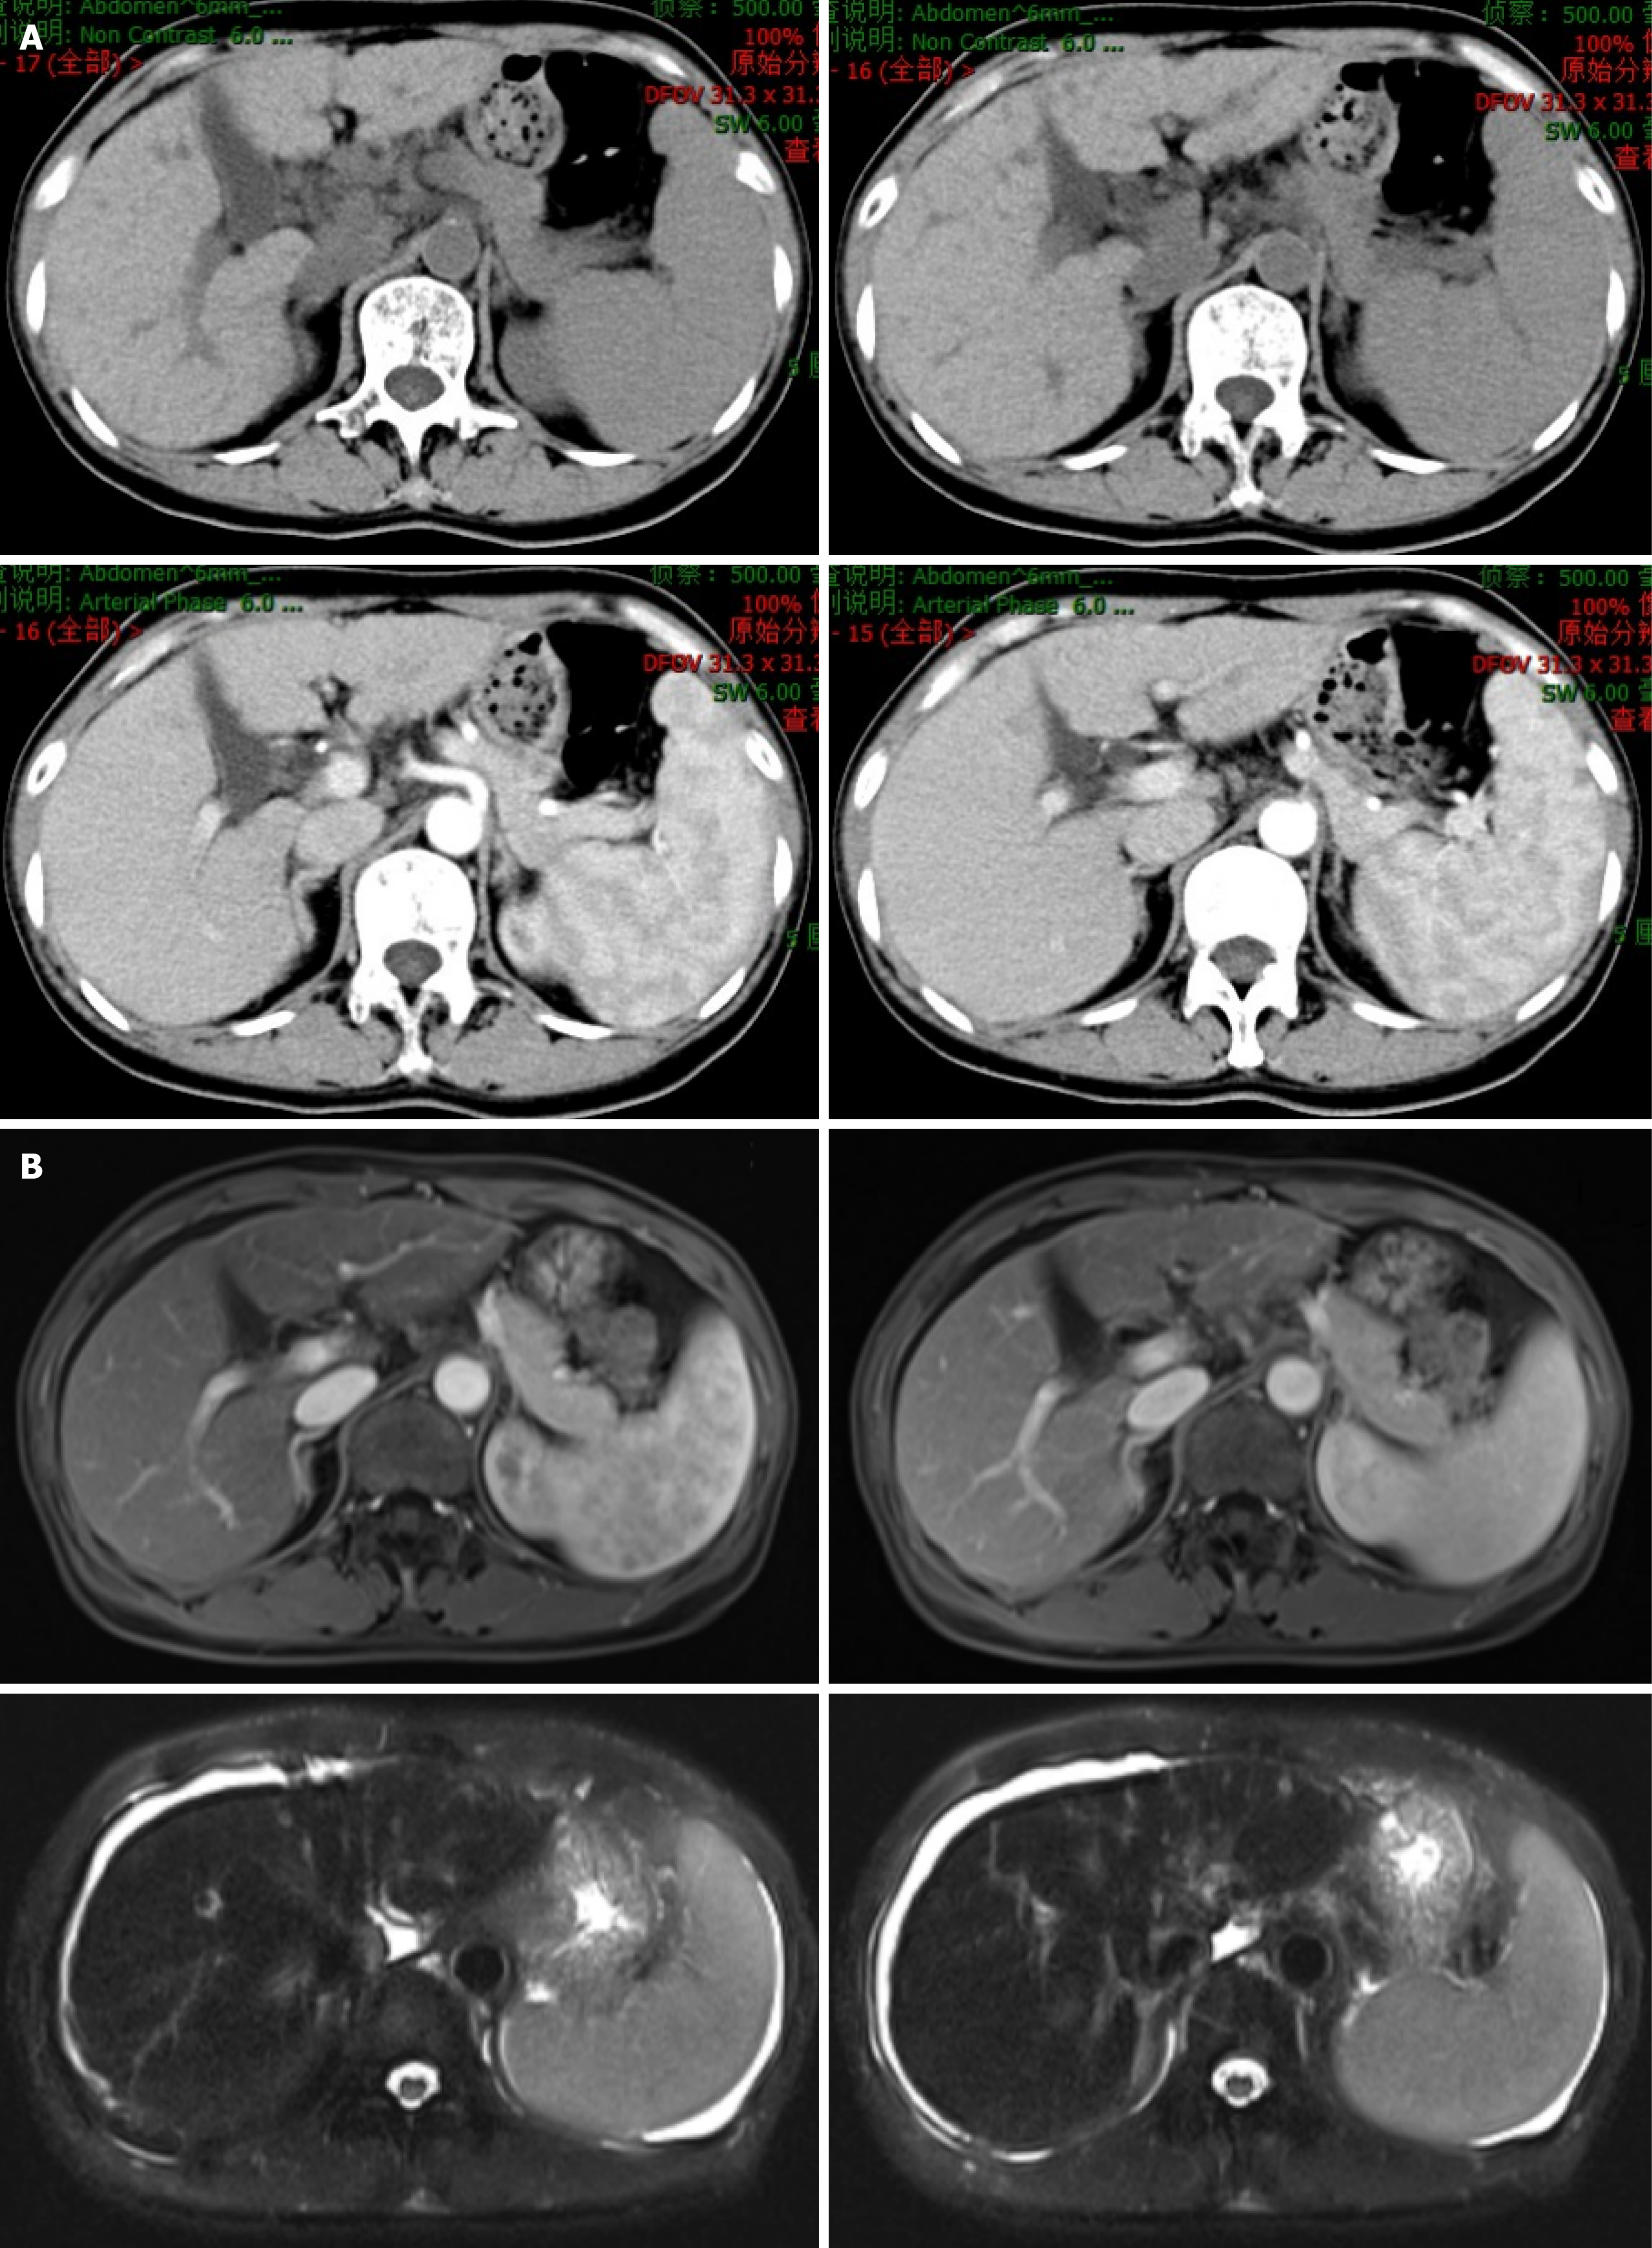

Figure 3 Abdominal magnetic resonance imaging and computed tomography findings of cirrhosis during follow-up.

A: Upper abdominal computed tomography (plain and enhanced) scans revealed irregular margins with slightly widened fissures, and strip low-density shadows around the portal vein in the liver; B: Upper abdominal magnetic resonance imaging revealed heterogeneous signal intensity with an irregular contour, slightly widened fissures, heterogeneous enhancement, and a long T2 signal around the portal vein in the liver. The spleen was enlarged. The upper abdominal magnetic resonance imaging findings indicated cirrhosis with splenomegaly and ascites. No abnormal enhancement was observed on the enhanced scan. The spleen was enlarged.